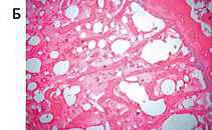

В рамках темы ведется работа по воспроизведению сахарного диабета 2 типа и менопаузы у самок крыс Wistar. Изучено влияние канаглифлозина и лираглутида на параметры фосфорно-кальциевого обмена и костное ремоделирование. Применение как низкоселективного иНГЛТ-2 канаглифлозина, так и арГПП-1 лираглутида значимо не повлияло на параметры костного ремоделирования. В то же время применение канаглифлозина привело к снижению количества костных балок эпифизарной области бедренной кости, что может говорить об активации костной резорбции на фоне применения данного препарата.

Влияние терапии современными сахароснижающими препаратами на показатели костного обмена в условиях экспериментальной модели сахарного диабета и овариэктомии. Тимкина Н.В., Семенова Н.Ю., Симаненкова А.В., Цинзерлинг В.А., Власов Т.Д., Байрамов А.А., Хальзова А.К., Шимшилашвили А.А., Тимофеева В.А., Каронова Т.Л. Сахарный диабет. — 2023. — Т. 26, № 2. — С. 145—156. — DOI: 10.14341/DM12967. Scopus Q3/Q4. IF 3,178